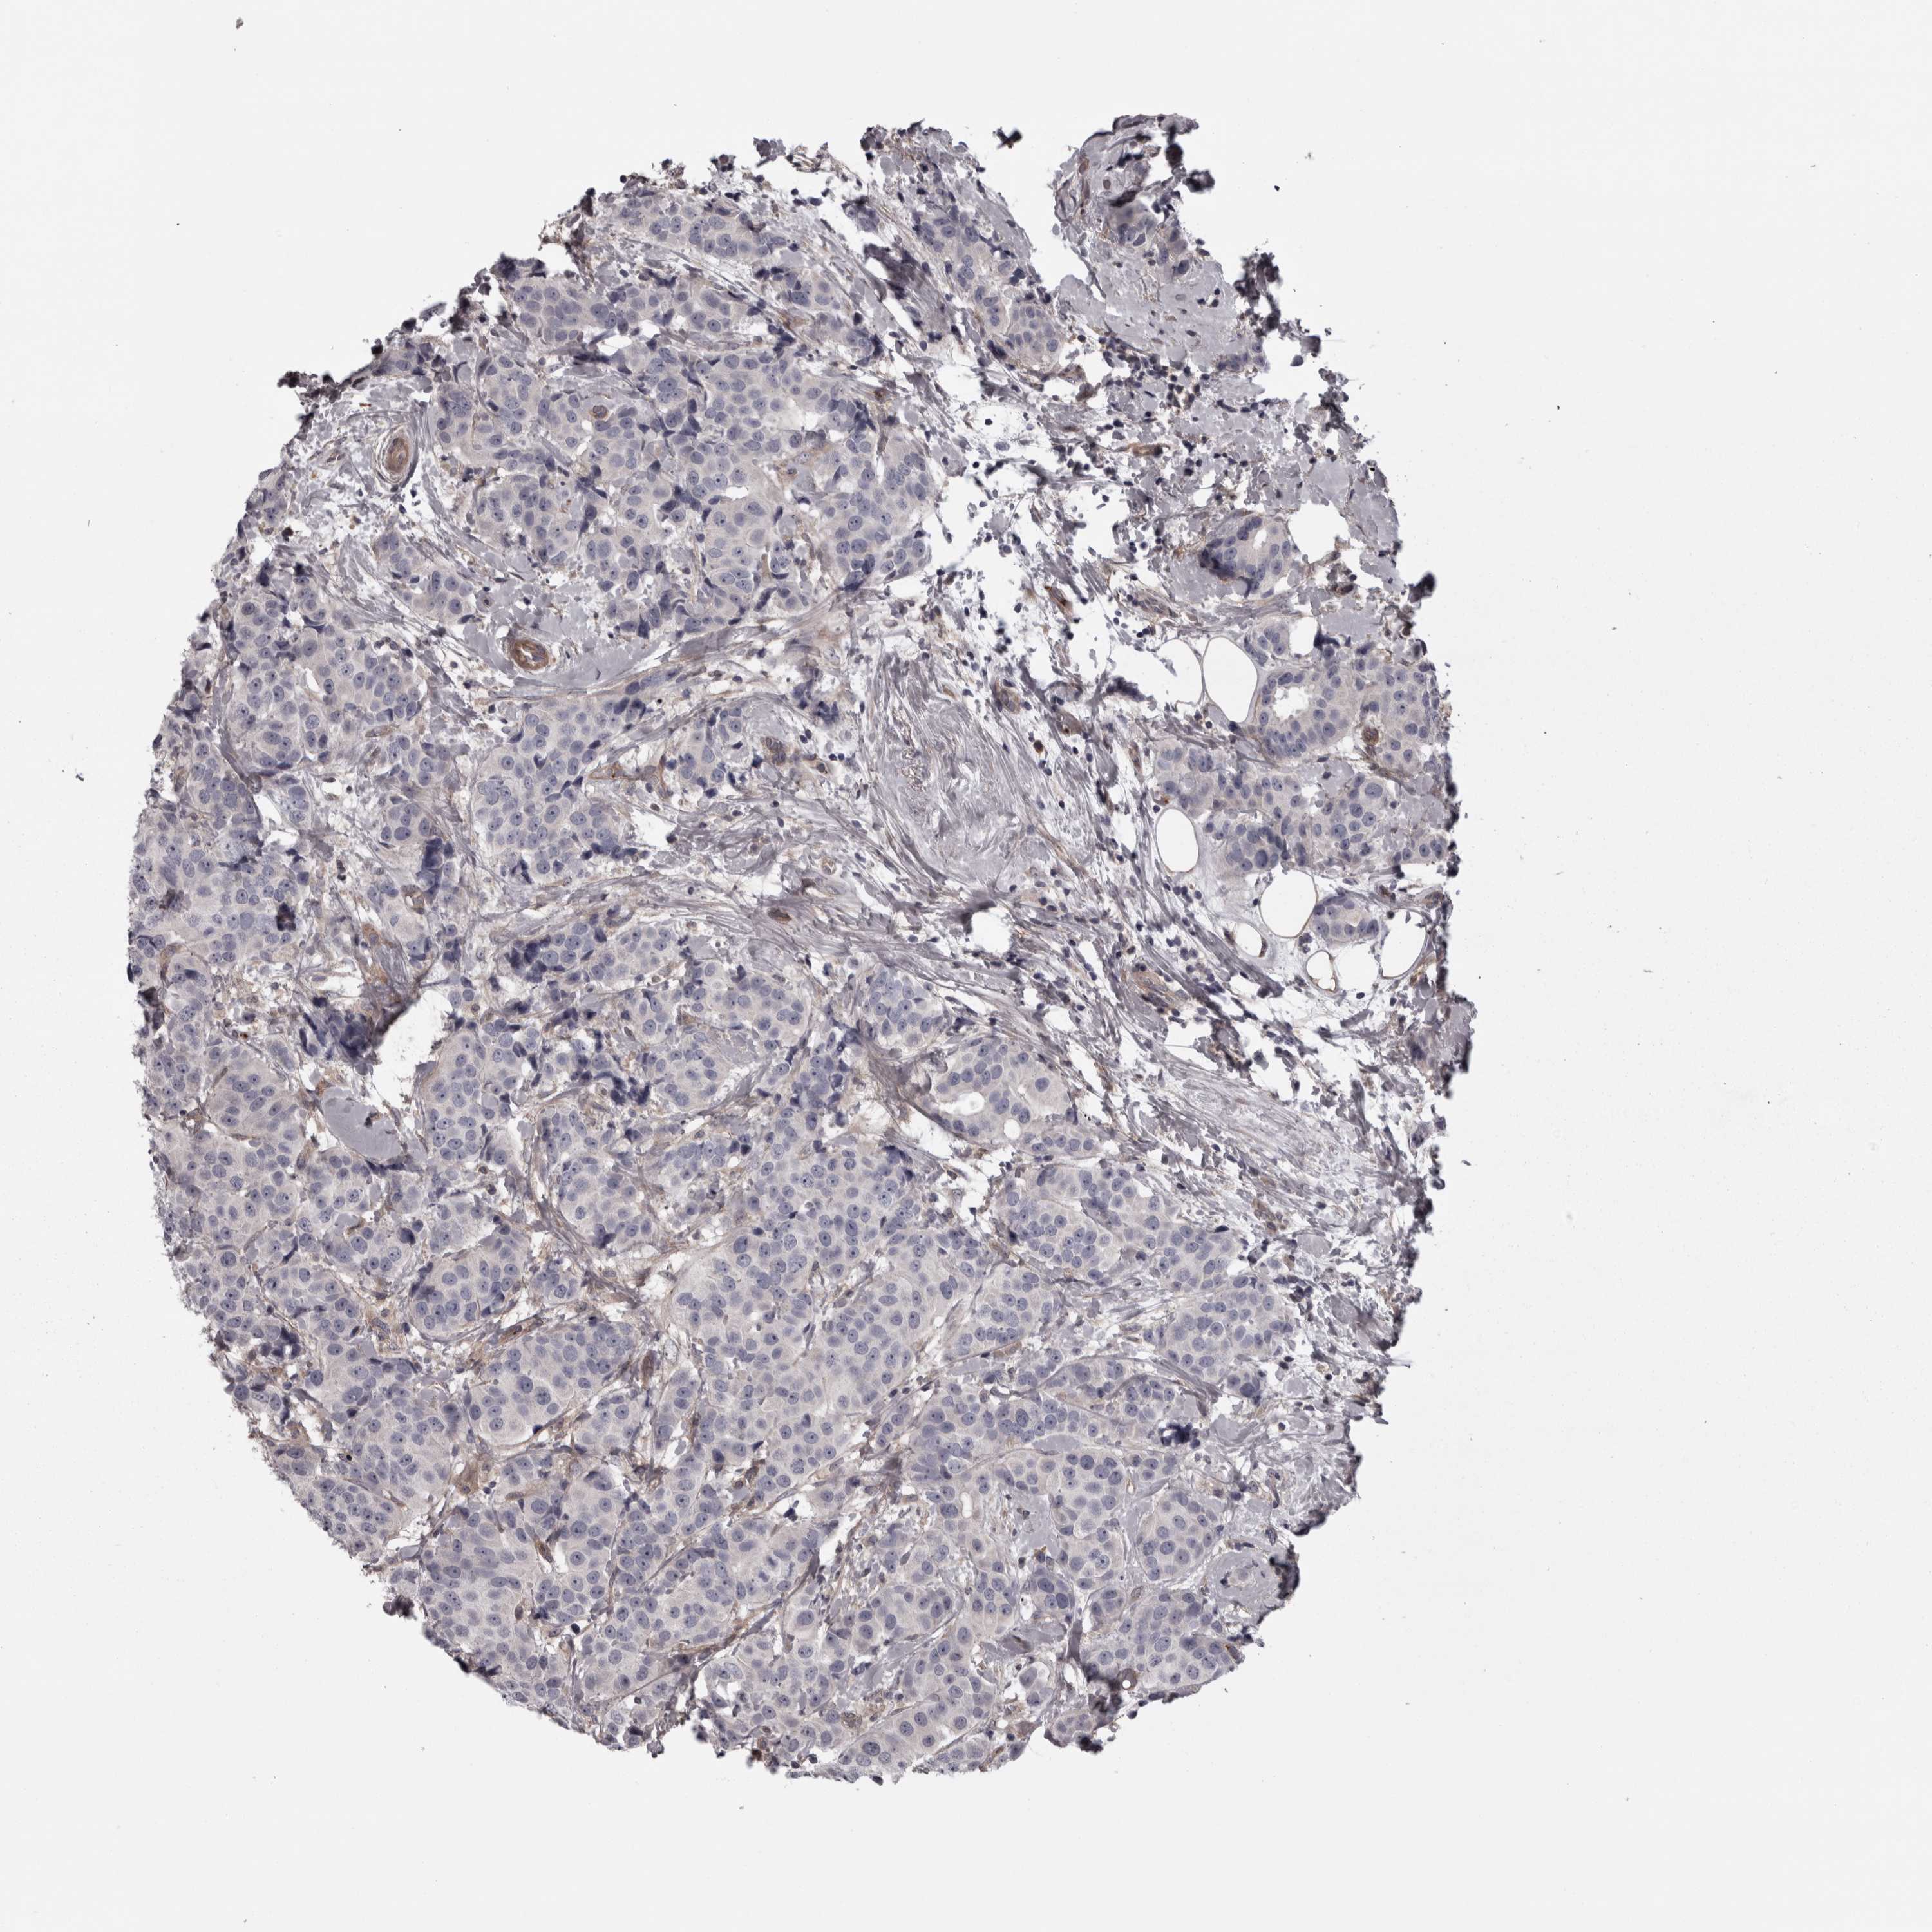

CANCER BREAST CANCER Show tissue menu

BRCA TCGA BRCA VALIDATION PROTEIN EXPRESSION